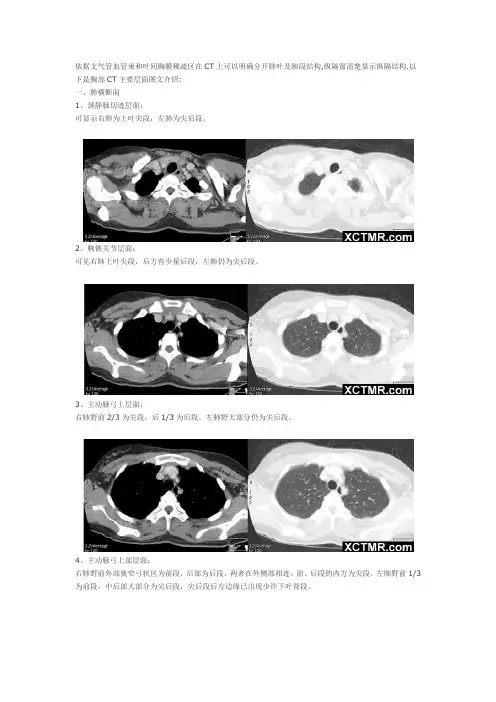

依据支气管血管束和叶间胸膜稀疏区在CT上可以明确分开肺叶及肺段结构,纵隔窗清楚显示纵隔结构.以下是胸部CT主要层面图文介绍:一、肺横断面1、颈静脉切迹层面:可显示右肺为上叶尖段,左肺为尖后段。

2、胸锁关节层面:可见右肺上叶尖段,后方有少量后段,左肺仍为尖后段。

3、主动脉弓上层面:右肺野前2/3为尖段,后1/3为后段。

左肺野大部分仍为尖后段。

4、主动脉弓上部层面:右肺野前外部狭窄弓状区为前段,后部为后段,两者在外侧部相连。

前、后段的内方为尖段。

左肺野前1/3为前段,中后部大部分为尖后段,尖后段后方边缘已出现少许下叶背段。